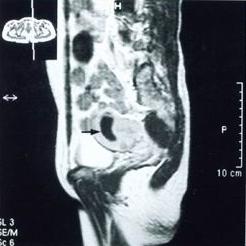

妇科检查时见子宫后屈,活动差,子宫旁可扪及增粗的输卵管,有压痛。如果有炎性包块形成,检查时可在宫旁或子宫后方触及包块,活动不良,有压痛。在女性内生殖器官中,输卵管、卵巢被称为子宫附件。 医学百科网 | YxBaike.Com

盆腔的位置慢性盆腔炎患者早期全身症状多不明显,一般仅为程度不同的、时轻时重的下腹疼痛,或下腹坠胀或牵扯感,月经前、劳累后或性交后加重,并常伴有大便时的腹坠感,白带增多、腰痛、月经失调等,也可因输卵管粘连造成宫外孕或不孕症。